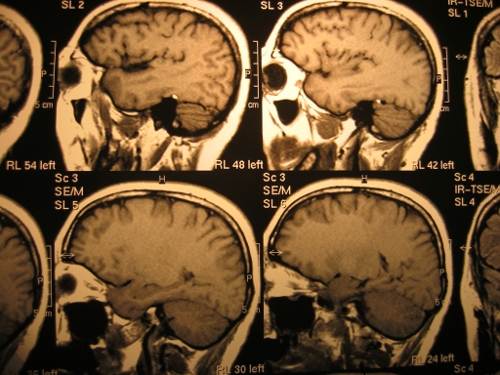

Il team di ricercatori ha utilizzato l’ecodoppler per esaminare il flusso di sangue venoso nei pazienti in diverse posture, e la risonanza magnetica per individuare, nel cervello, i depositi di ferro.

Queste impedirebbero al sangue di circolare abbastanza velocemente, e ciò causerebbe come conseguenza il danneggiamento del cervello, causato dall’accumulo di ferro. Una delle sperimentazioni effettuate dallo studioso italiano è stata proprio il tentativo di allargare le vene nei tessuti cerebrali.